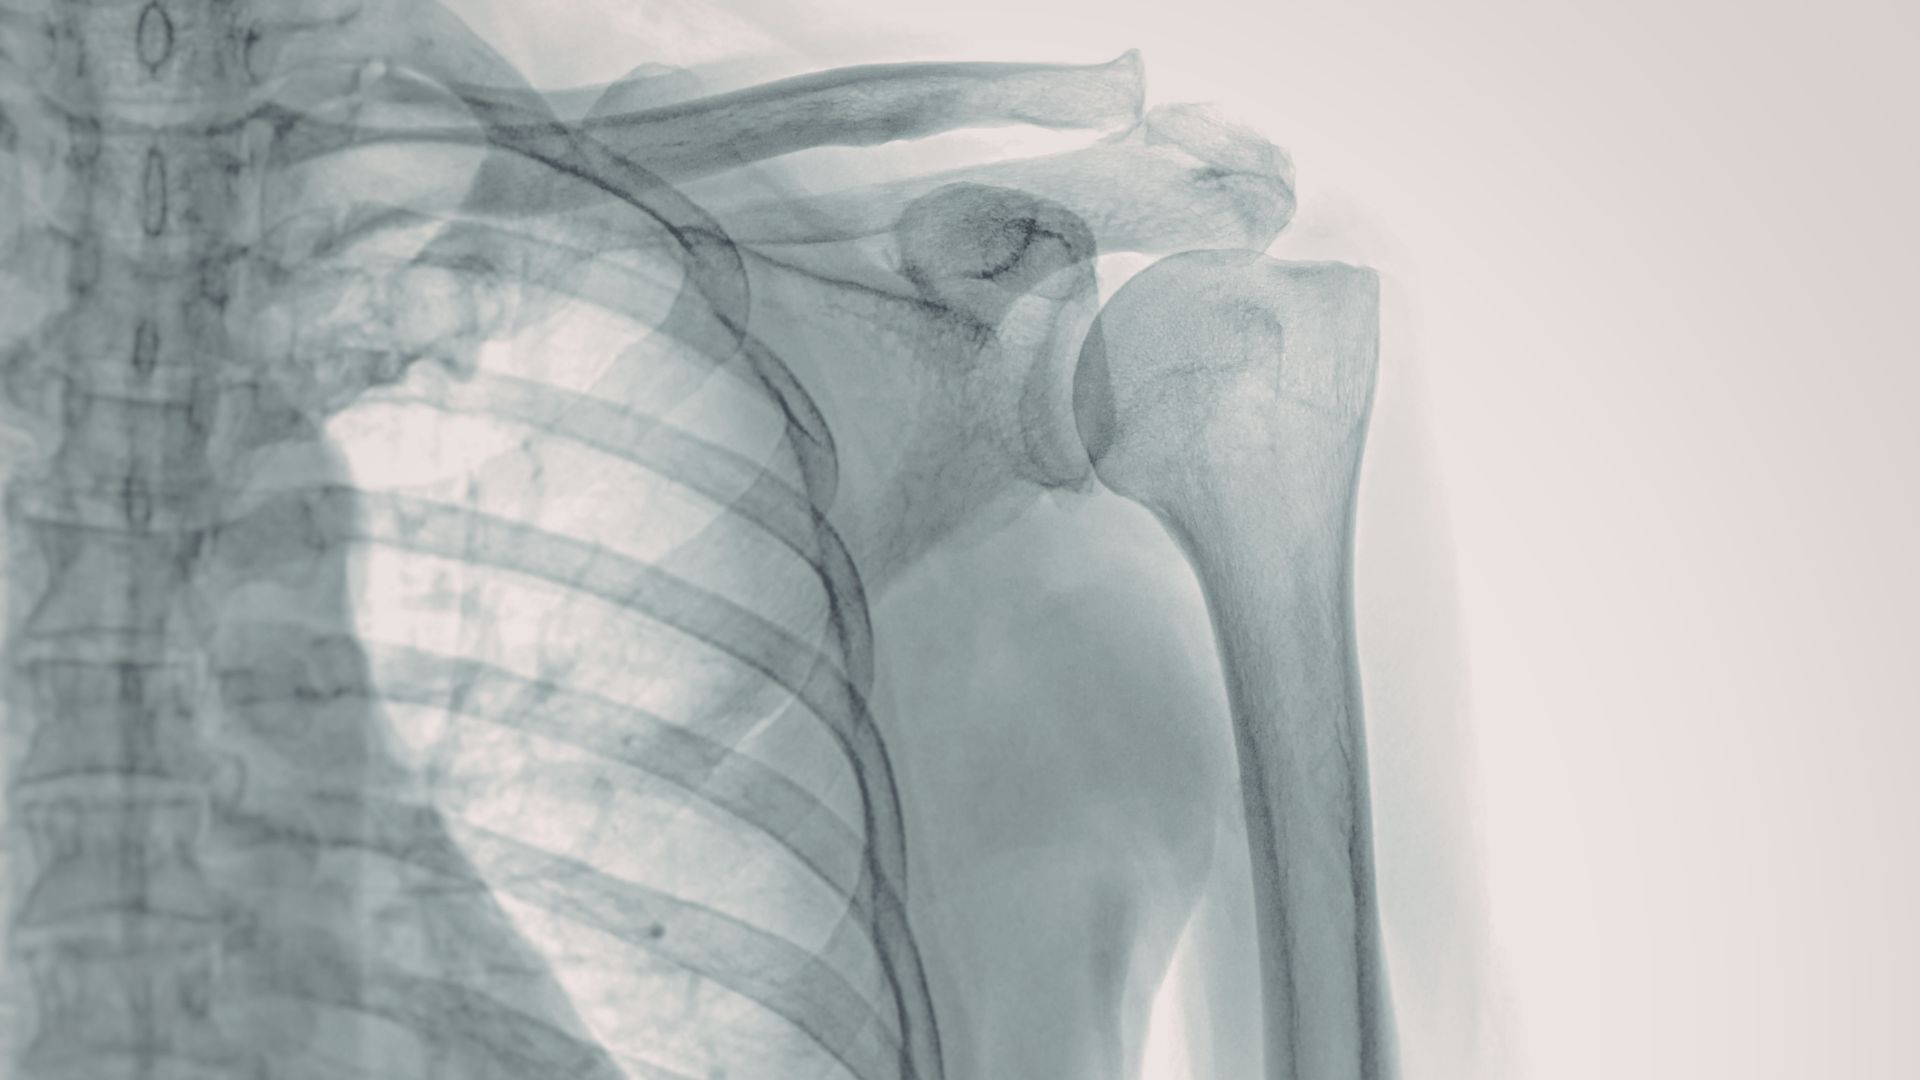

Vai trò của X-quang khớp vai trong chẩn đoán và điều trị

Để xác định chính xác nguyên nhân và mức độ tổn thương, bác sĩ cần kết hợp thăm khám với các phương tiện chẩn đoán hình ảnh phù hợp. Trong đó, X-quang được xem là kỹ thuật nền tảng, đóng vai trò quan trọng trong cả chẩn đoán ban đầu lẫn theo dõi điều trị. Một số vai trò của X-quang khớp vai có thể nhắc đến như:

- Phát hiện tổn thương xương trong chấn thương cấp tính: X-quang khớp vai là kỹ thuật đầu tay khi nghi ngờ gãy xương, trật khớp hoặc nứt xương sau té ngã, tai nạn. Hình ảnh thu được giúp xác định vị trí, mức độ di lệch và phạm vi tổn thương, từ đó hỗ trợ quyết định điều trị bảo tồn hay phẫu thuật.

- Đánh giá các bệnh lý thoái hóa khớp vai: Ở người trung niên và cao tuổi, X-quang giúp phát hiện hẹp khe khớp, gai xương, đặc xương dưới sụn là những dấu hiệu đặc trưng của thoái hóa. Đây là cơ sở quan trọng để xây dựng phác đồ điều trị phù hợp.

- Hỗ trợ chẩn đoán bệnh lý viêm và lắng đọng canxi: Trong một số trường hợp đau vai kéo dài, X-quang có thể phát hiện lắng đọng canxi quanh gân hoặc biến đổi cấu trúc khớp do viêm mạn tính.

- Theo dõi hiệu quả điều trị và hậu phẫu: Sau bó bột, nắn chỉnh hoặc phẫu thuật kết hợp xương, X-quang được sử dụng để kiểm tra sự liền xương, vị trí dụng cụ cố định và phát hiện biến chứng nếu có.

- Định hướng chỉ định các phương tiện chẩn đoán chuyên sâu hơn: Khi hình ảnh X-quang chưa đủ để giải thích triệu chứng, bác sĩ có thể chỉ định thêm siêu âm, chụp CT hoặc MRI dựa trên kết quả ban đầu.